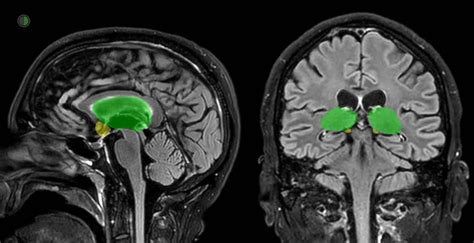

The thalamus is a small, egg-shaped structure located deep within the brain, situated between the cerebral cortex and the midbrain. It serves as a relay center, processing and transmitting sensory information to the cerebral cortex. The thalamus is involved in various functions, including:

The hypothalamus is a small, pea-sized structure located at the base of the brain, just below the thalamus. It plays a critical role in maintaining the body's homeostasis by regulating various physiological processes, including: